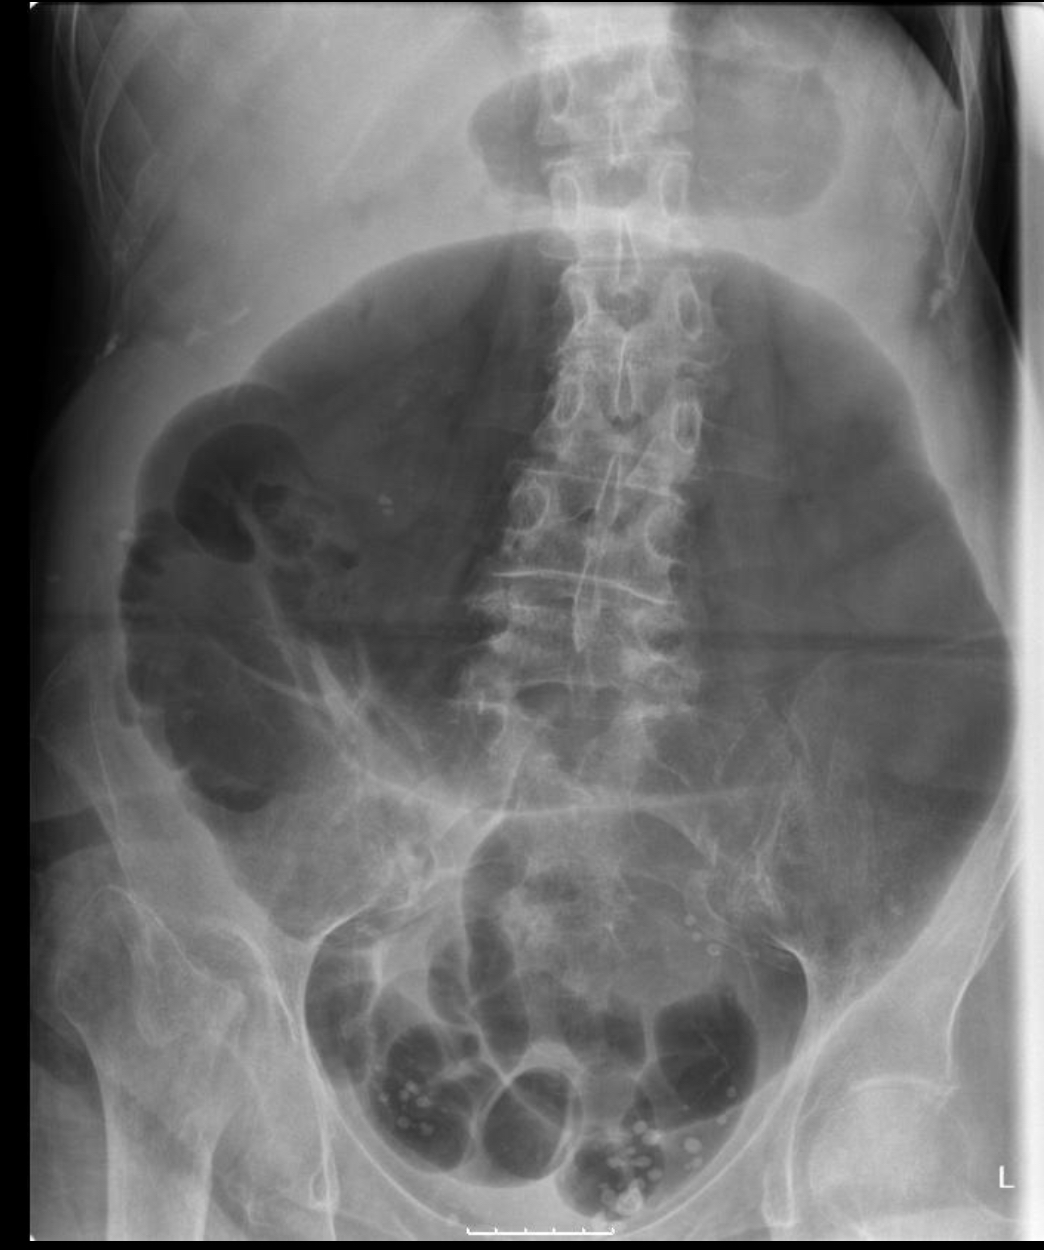

What pathology is this?

Bowel obstruction

partial or full blockage of large or small bowel that does not allow substances to pass through

radiographic appearance of bowel obstruction

dilation of bowel

technical factors of bowel obstruction

depending on blockage, may need to increase/decrease